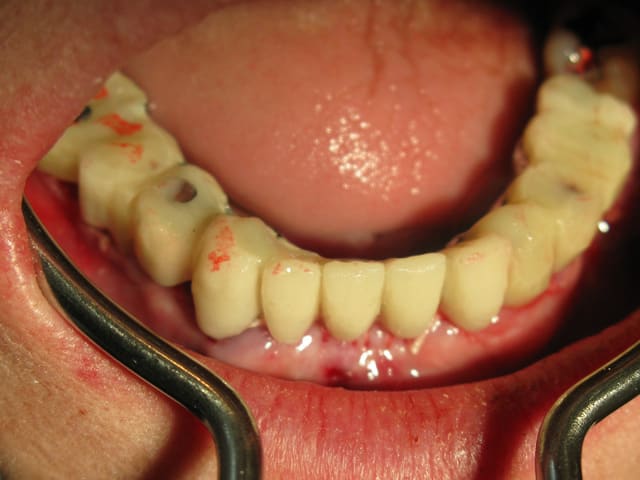

Extraction MCI en une opération.

22/03/2009 à 19h26

o.k. mais le trip reste le même que tu le fasses en une fois ou huit jours après. La bague de cica est déjà une mise en vitrine. D'autre part ce genre de truc ça gonfle tellement les premiers jours que ta patiente ne va pas sourire des masses ni même bouffer dans le secteur... Il faut relativiser d'autant plus qu'ici je me retrouvais short pour le calage primaire et tu noteras la classe II... La mise en place de la provisoire a eu lieu au retrait des sutures. Et il ne pourra pas s'agir d'une mise en charge, simplement d'une mise en vitrine.

Le didacticiel répondait à la question de Pluton qui se rendra vite compte que la mise en vitrine immédiate en zone prémaxillaire est un objectif peut-être souvent poursuivi mais plus rarement atteint. Mais peut-être qu'ailleurs l'herbe est plus verte ?